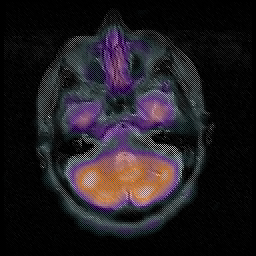

Huntington's Chorea, MR -- Slice #3

[Home][Help][Clinical] Slice 3